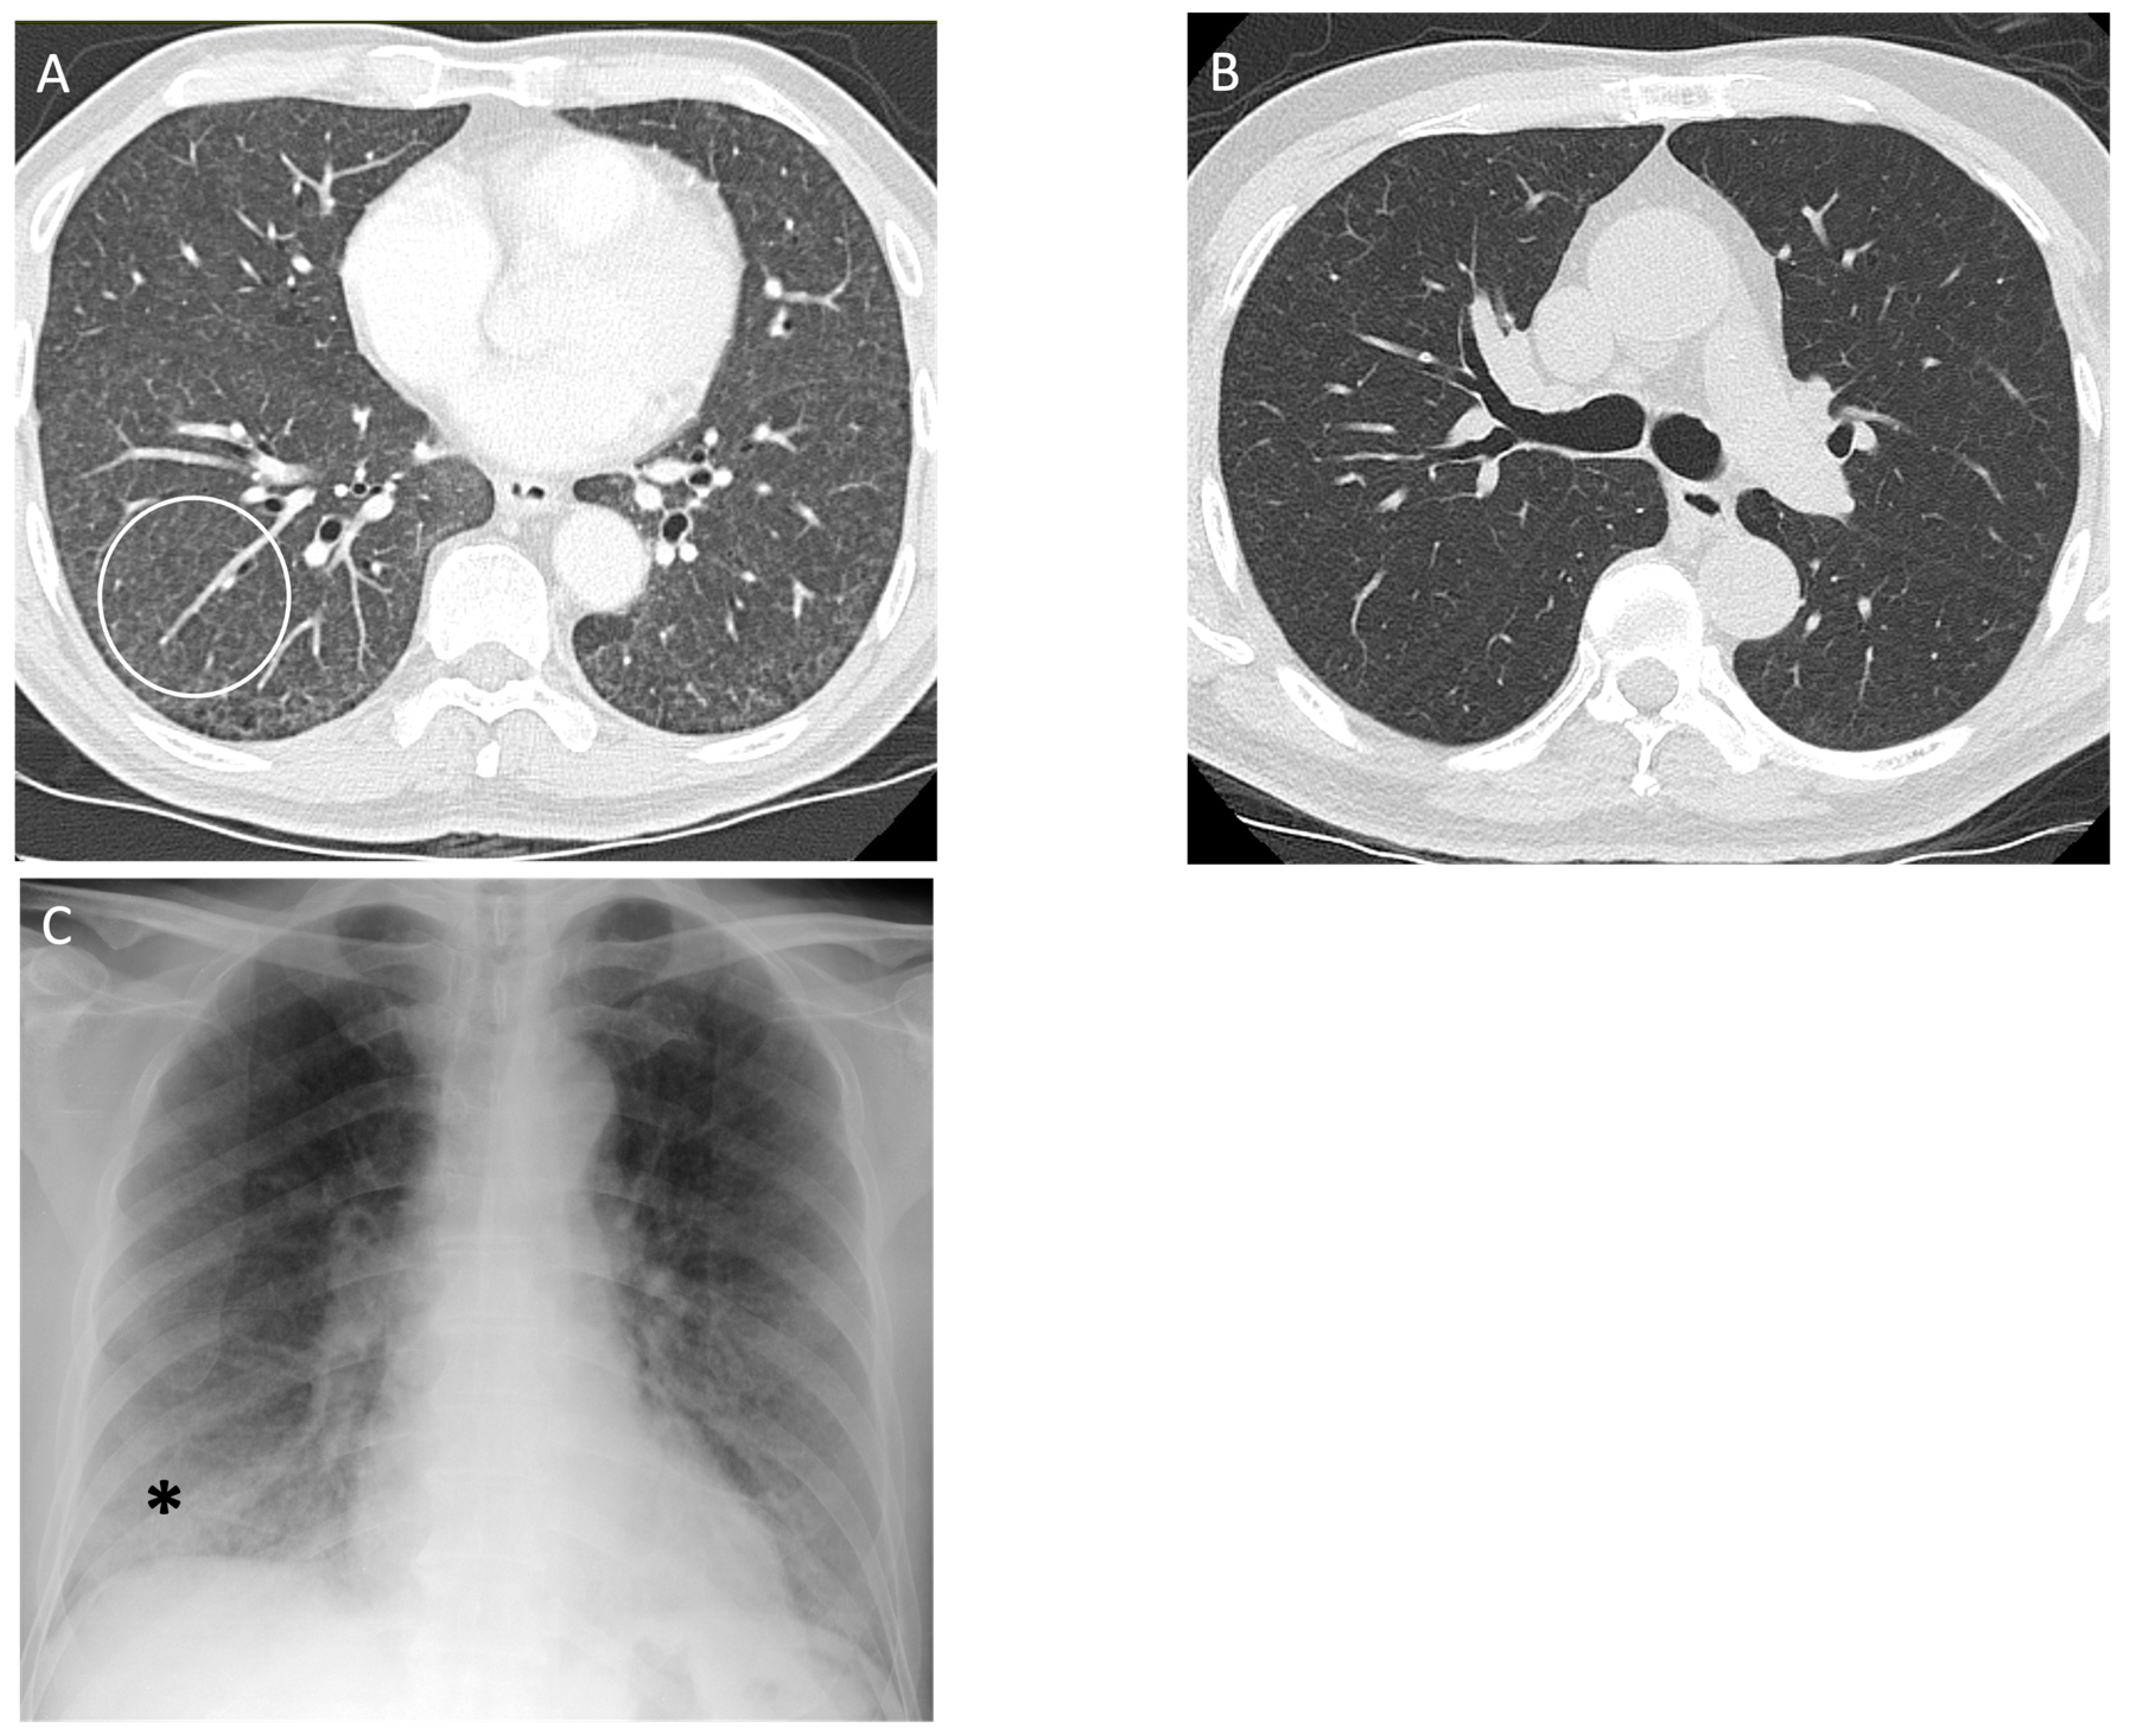

5. Hypersensitivity Pneumonitis

| Hypersensitivity Pneumonitis | Non-fibrotic: diffuse ground glass opacities, nodules/consolidation present, centrilobular nodules [72] Fibrotic: peribronchiovascular fibrosis, small airway disease [67,72] | Difficult to differentiate by imaging only; evidence of ground glass opacities and air trapping along with bronchioalveolar lavage lymphocytosis aids diagnosis [66] |